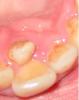

aleksandr Опубликовано 29 ноября, 2008 Автор Поделиться Опубликовано 29 ноября, 2008 (изменено) Хорошо бы увидеть рентгеновский снимок. Ну, или хотя бы фотографию проблемных зубов. Изменено 29 ноября, 2008 пользователем aleksandr Ссылка на комментарий

irenika Опубликовано 29 ноября, 2008 Поделиться Опубликовано 29 ноября, 2008 а можно снимок пошире,чтобы зубной ряд было видно в области шести зубов.у меня сложилось впечатление,что это клык.постояннй клык.просто он прорезался не на своем месте,а небно и еще в обл.резцов. Ссылка на комментарий

АНРОША Опубликовано 29 ноября, 2008 Поделиться Опубликовано 29 ноября, 2008 а можно снимок пошире,чтобы зубной ряд было видно в области шести зубов.у меня сложилось впечатление,что это клык.постояннй клык.просто он прорезался не на своем месте,а небно и еще в обл.резцов.Мне кажется, что мелковат зубик для постоянного клыка. Сверхкомплектный. Удалять. Ссылка на комментарий

irenika Опубликовано 30 ноября, 2008 Поделиться Опубликовано 30 ноября, 2008 Мне кажется, что мелковат зубик для постоянного клыка. Сверхкомплектный. Удалять.а он развернут и не вертикально режется.здесь не всю коронку видно. Ссылка на комментарий

АНРОША Опубликовано 30 ноября, 2008 Поделиться Опубликовано 30 ноября, 2008 а он развернут и не вертикально режется.здесь не всю коронку видно.возможно, конечно... без панорамного снимка гадать можно долго Ссылка на комментарий